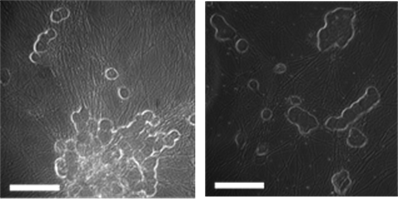

Figure 1 shows paired phase‑contrast (top row) and calcium dye fluorescence images (bottom row) from the same fields of view in cultured mouse DRG neurons. Panel (a) depicts cells in 0.1% DMSO; panel (b) shows cells exposed to a Nav1.8 inhibitor during an acid challenge (pH 5.7), as labeled. The phase images documented comparable cell‑body morphology and attachment, while the matched fluorescence frames visualized the spatial distribution of Ca²⁺‑responsive cells (bright puncta) at the time of response. These micrographs were intended as qualitative context—to illustrate the fields used for ROI selection and registration—and complement the quantitative time‑series analysis of ΔF/F₀, FWHM, and AUC reported elsewhere, rather than serving as a direct intensity comparison between conditions.

(a) (b)

(c) (d)